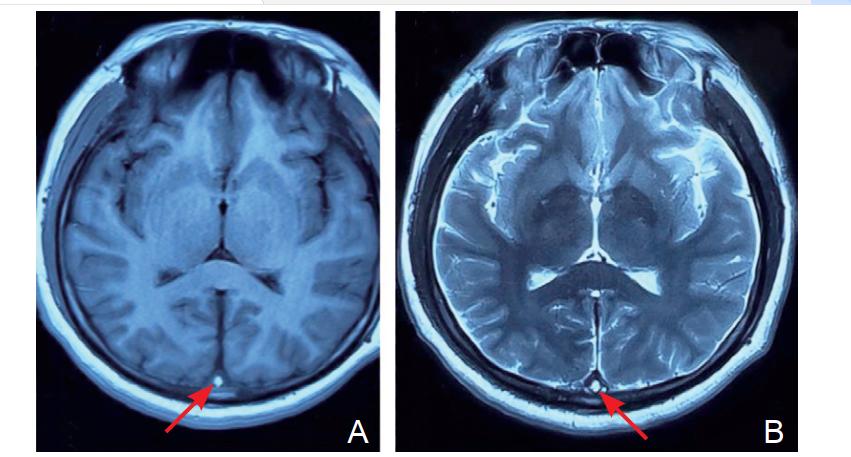

(3)影像学检查:首选的检查方法为MRI,建议包括GRE及SWI序列,以显示微小病灶和可能存在的发育性畸形。

图7 A:T2加权MRI提示右枕叶单发海绵状血管畸形;B:梯度回波T2加权成像提示多发海绵状血管畸形(4)治疗:无症状患者一般建议采取保守治疗,多发的无症状患者也不建议进行外科处理。对于症状性、有出血史且位于浅部手术易于切除的患者,建议积极手术处理,尤其是位于非功能区的患者。症状性深部病灶建议结合并且具体考虑。